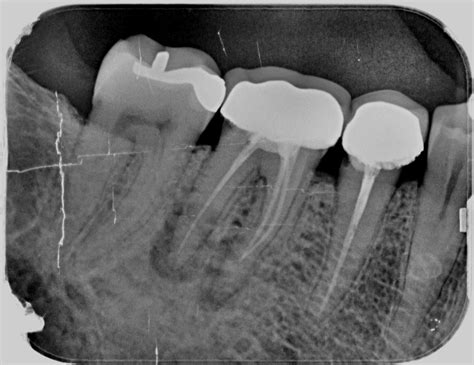

Radiografía de una endodoncia mal hecha

Una de las herramientas más seguras y fiables para detectar una endodoncia fracasada es la radiografía dental. En estas radiografías se pueden observar diferentes problemas:

- Sobreobturación: cuando el material de obturación se extiende más allá de la raíz, puede irritar los tejidos periapicales.

- Lesiones periapicales: se identifican como áreas más oscuras o radiotransparentes alrededor del ápice del diente. Lesión periapical: entre el 2 y el 14% de las endodoncias fracasan provocando inflamación periapical en los tejidos que rodean la raíz del diente.

- Conductos no tratados: puede que existan conductos adicionales sin tratar, los cuales aparecen como áreas radiotransparentes, ya que no han sido limpiados ni rellenados. No haber localizado un conducto. Cada diente tiene un número de conductos o nervios, y deben eliminarse y sellarse todos ellos. Aunque anatómicamente un molar suele tener tres conductos, existen casos en los que pueden tener cuatro e incluso cinco.

- Fracturas radiculares: aunque a veces son difíciles de detectar, pueden verse como líneas finas y oscuras a lo largo de la raíz. Existencia de una fisura o fractura vertical del diente. Muchas veces la endodoncia está bien hecha. Pero es posible que el diente tenga una fisura o una fractura dificil de diagnosticar, incluso con radiografías.